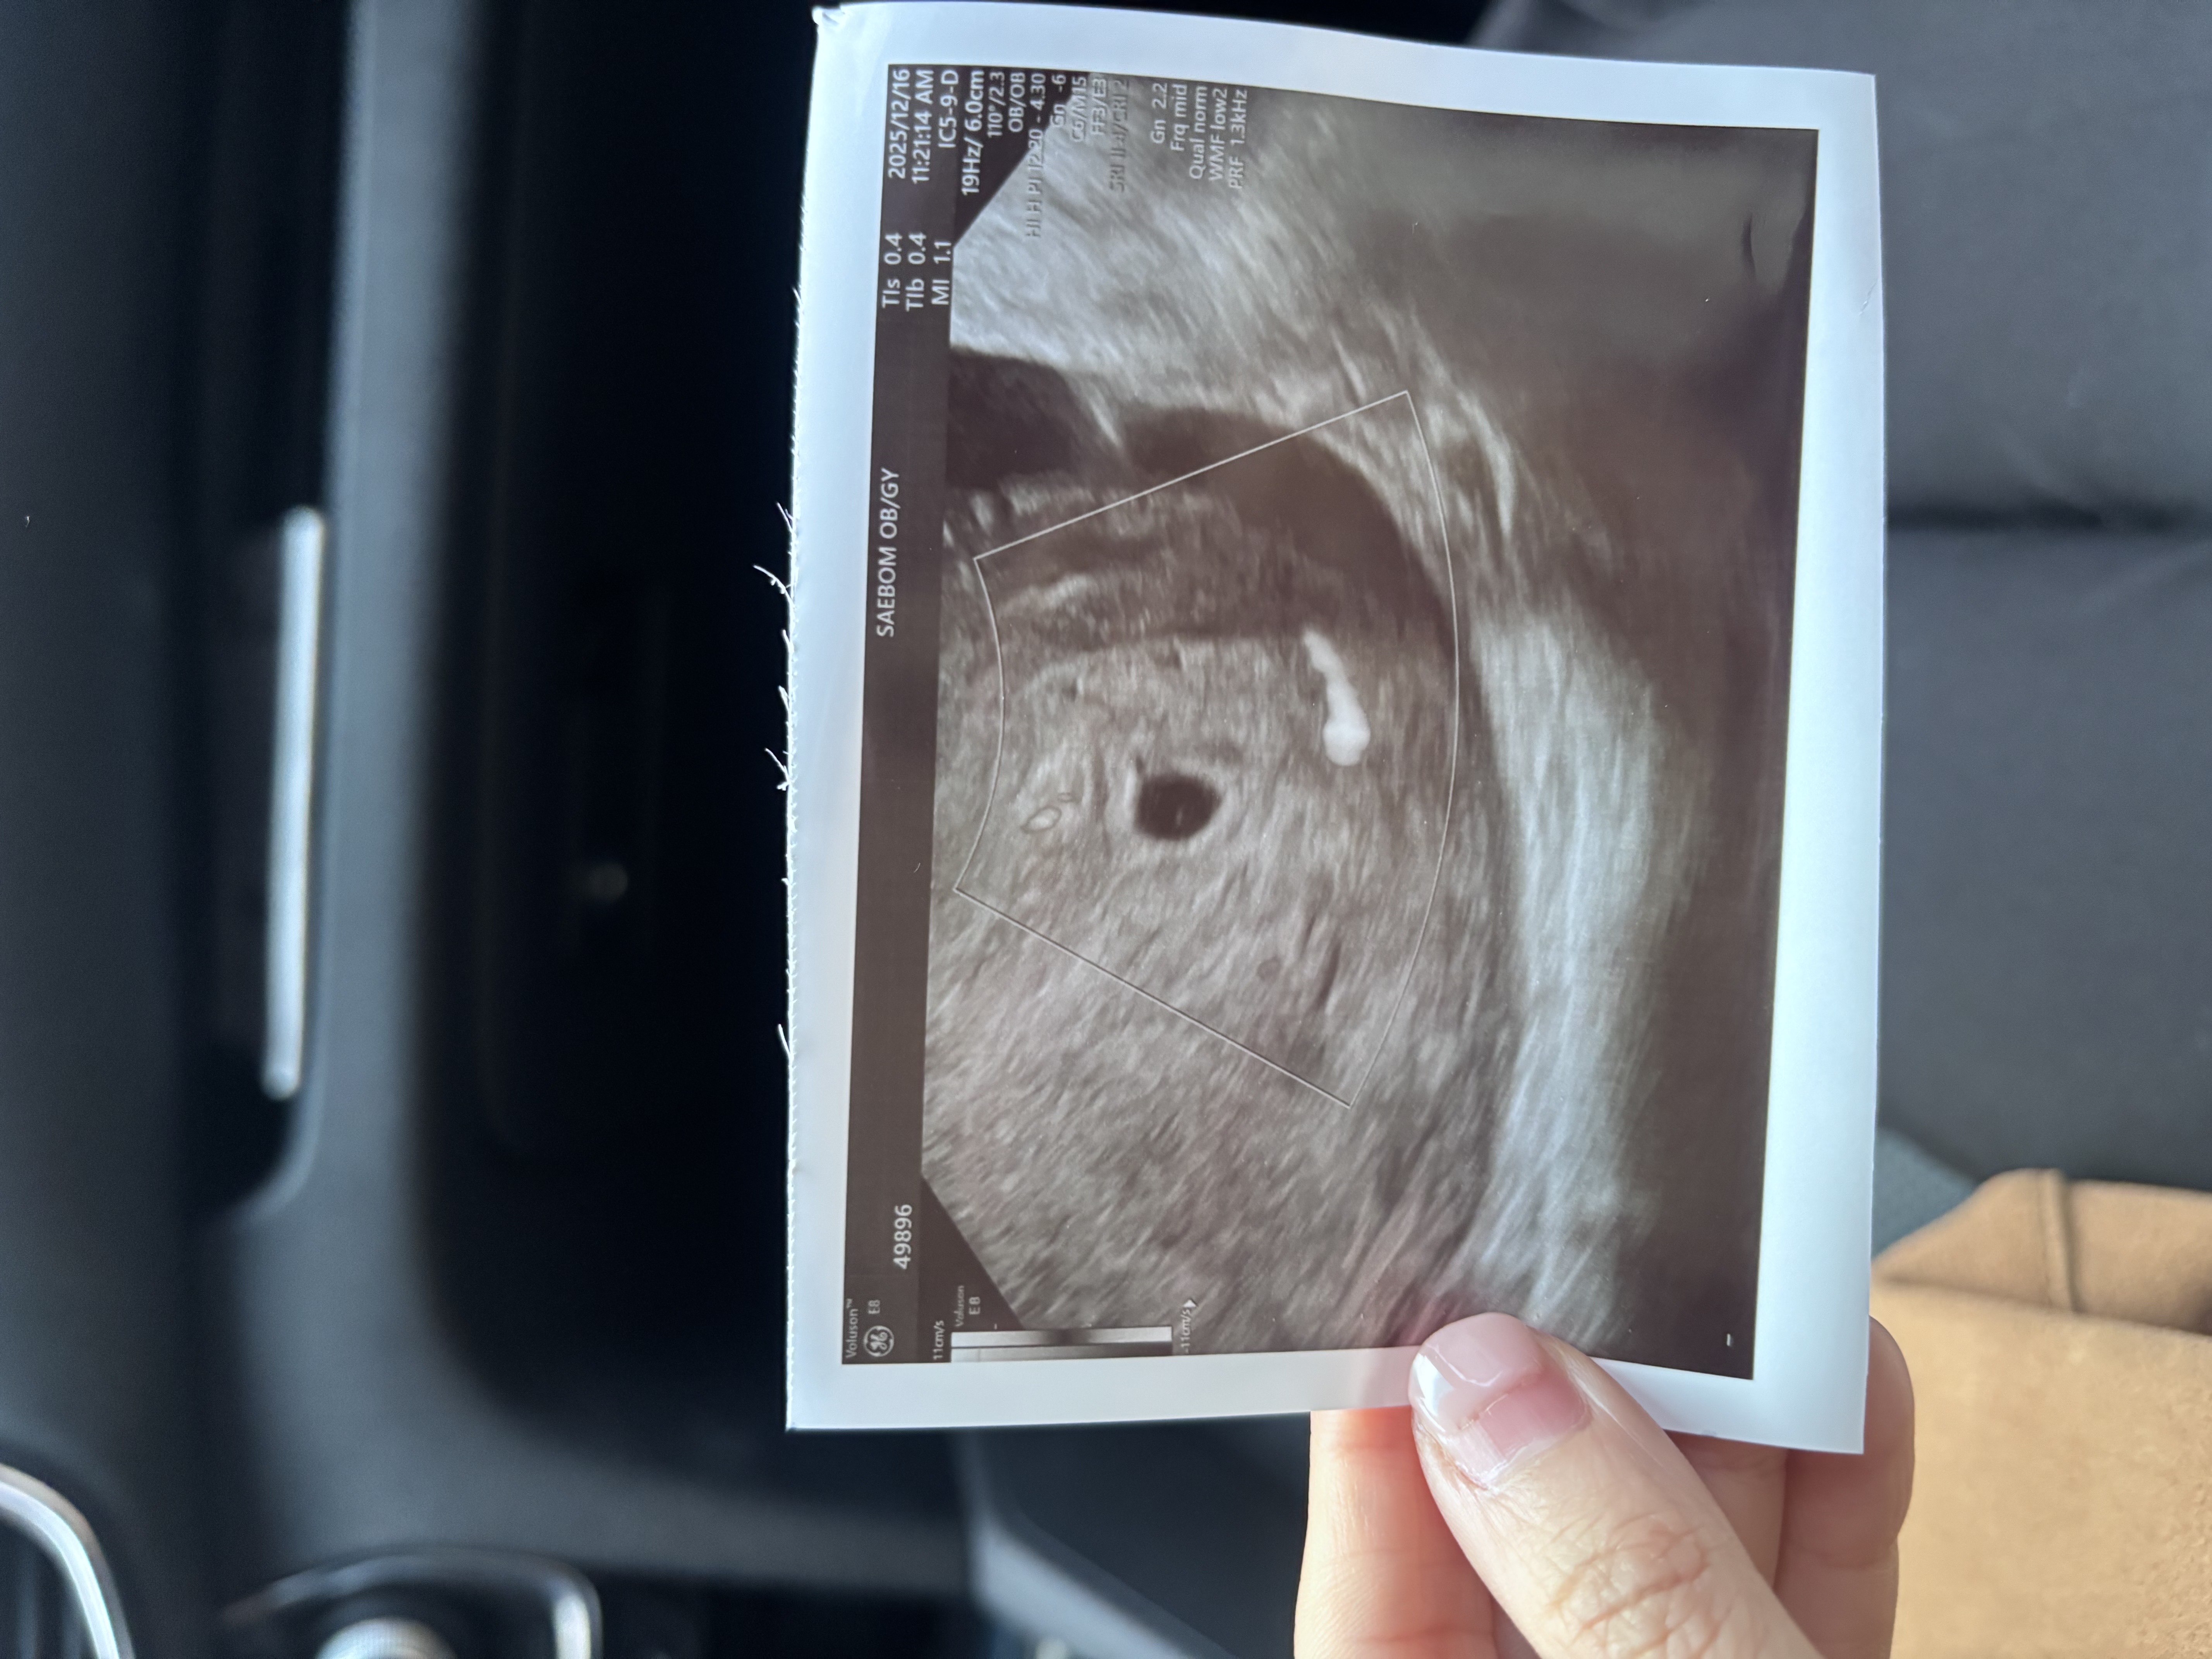

아기집안에 동그라미 난황같아요!

아기집 보고왔는데 성장이 10일정도 더딘 편이라하셔서 걱정이에요ㅠㅠㅠㅠㅠ 금욜에는 난황이 보여야한다하시는데... 아기집안에 희미하게 보이는 하얀 점은 난황이 아닌가요...?ㅠㅠㅠㅠ

그럴까요?? 그럼 진짜 너무너무 좋을거같은데ㅠㅠㅠㅠㅠ 다른 병원가서 초음파보니 또 아무것두 안보이더라구요..